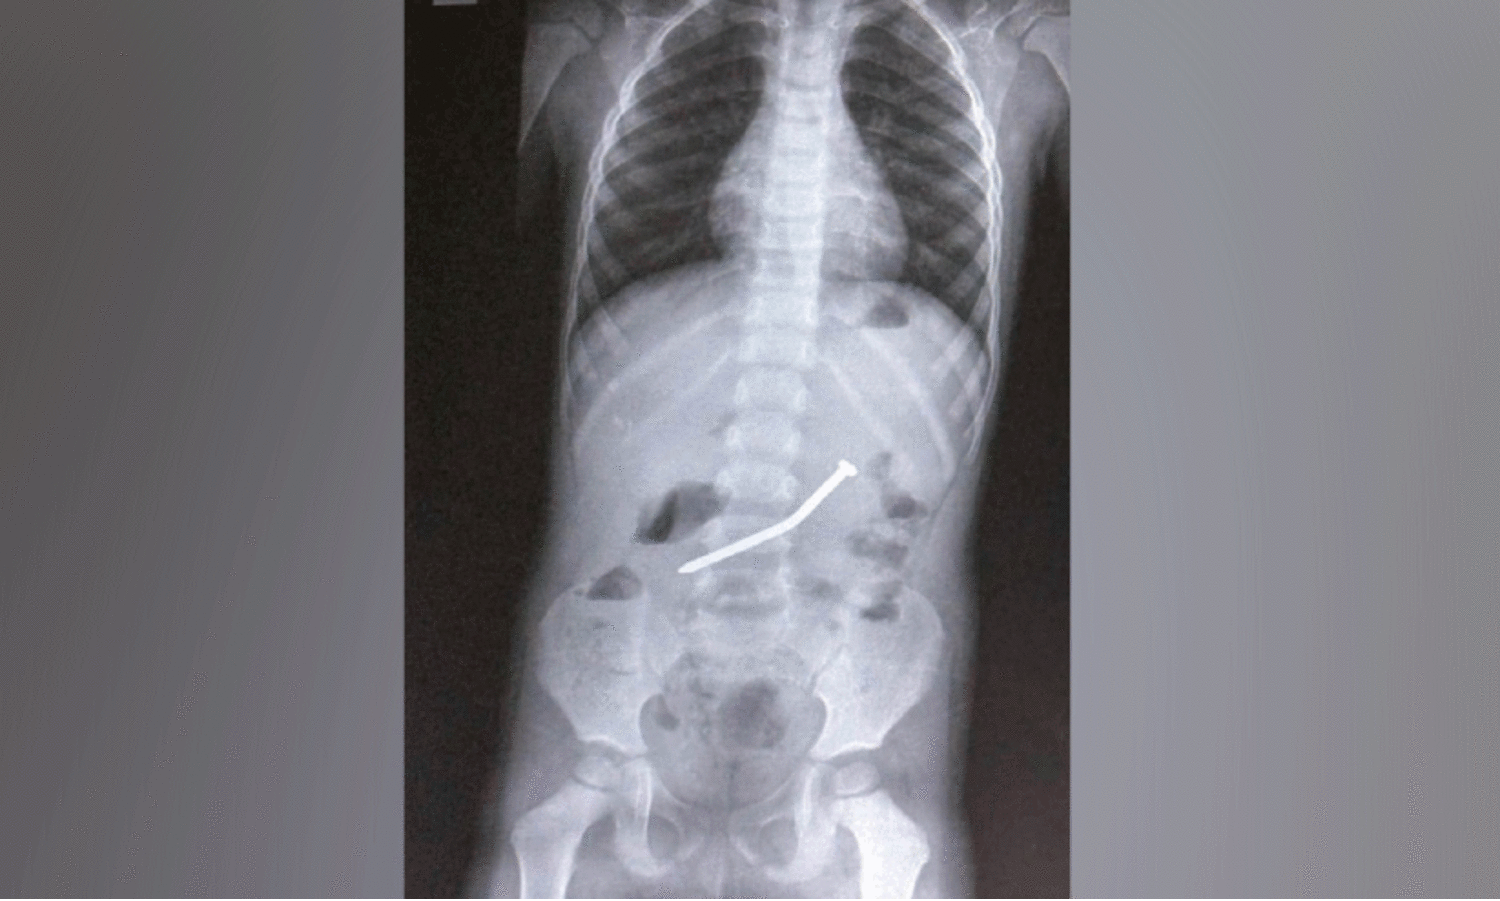

കു​ട്ടി​യു​ടെ ചെ​റു​കു​ട​ലി​ൽ ര​ണ്ട​ര ഇ​ഞ്ച് നീ​ള​മു​ള്ള ആ​ണി

മേ​പ്പാ​ടി: മു​ട്ടി​ൽ കു​ട്ട​മം​ഗ​ലം സ്വ​ദേ​ശി​ക​ളാ​യ ദ​മ്പ​തി​മാ​രു​ടെ ര​ണ്ട​ര വ​യ​സു​കാ​ര​ന്റെ വ​യ​റ്റി​ൽ അ​ക​പ്പെ​ട്ട ര​ണ്ട​ര ഇ​ഞ്ച് നീ​ള​മു​ള്ള വ​ണ്ണം കൂ​ടി​യ ഇ​രു​മ്പാ​ണി വി​ജ​യ​ക​ര​മാ​യി പു​റ​ത്തെ​ടു​ത്തു.ഡോ. ​മൂ​പ്പ​ൻ​സ് മെ​ഡി​ക്ക​ൽ കോ​ള​ജ് ഉ​ദ​ര-​ക​ര​ൾ രോ​ഗ വി​ഭാ​ഗം (ഗാ​സ്ട്രോ എ​ന്റ​റോ​ള​ജി) സീ​നി​യ​ർ സ്പെ​ഷ​ലി​സ്റ്റ് ഡോ.​ടി. ശ്രീ​നി​വാ​സ് റെ​ഡ്ഢിയാണ് ചെ​റു​കു​ട​ലി​ന്റെ തു​ട​ക്ക ഭാ​ഗ​ത്ത്(​ഡി​യോ​ഡി​നം) കു​ത്തി നി​ന്ന ആ​ണി എ​ൻ​ഡോ​സ്കോ​പ്പി​ലൂ​ടെ പു​റ​ത്തെ​ടു​ത്ത​ത്.

വീ​ട്ടി​ൽ ക​ളി​ച്ചു കൊ​ണ്ടി​രു​ന്ന കു​ട്ടി കൈ​യി​ൽ കി​ട്ടി​യ ആ​ണി വി​ഴു​ങ്ങു​ക​യാ​യി​രു​ന്നു. ഇ​ത് ക​ണ്ട മൂ​ത്ത കു​ട്ടി​യാ​ണ് മാ​താ​പി​താ​ക്ക​ളോ​ട് വി​വ​രം പ​റ​ഞ്ഞ​ത്. പി​ന്നീ​ട് പ​നി​യു​ടെ ല​ക്ഷ​ണ​ങ്ങ​ളോ​ടെ ക​ൽ​പ്പ​റ്റ ജ​ന​റ​ൽ ആ​ശു​പ​ത്രി​യി​ൽ പ്ര​വേ​ശി​പ്പി​ച്ച കു​ട്ടി​യു​ടെ എ​ക്സ്റേ വീ​ണ്ടു​മെ​ടു​ത്ത​പ്പോ​ൾ നേ​ര​ത്തേ ക​ണ്ട സ്ഥ​ല​ത്തു​നി​ന്നും ആ​ണി​യു​ടെ സ്ഥാ​നം മാ​റാ​ത്ത​തി​നെ തു​ട​ർ​ന്ന് വി​ദ​ഗ്ധ ചി​കി​ത്സ​ക്കാ​യി ഡോ. ​മൂ​പ്പ​ൻ​സ് മെ​ഡി​ക്ക​ൽ കോ​ള​ജി​ലേ​ക്ക് അ​യ​ക്കു​ക​യാ​യി​രി​ന്നു.